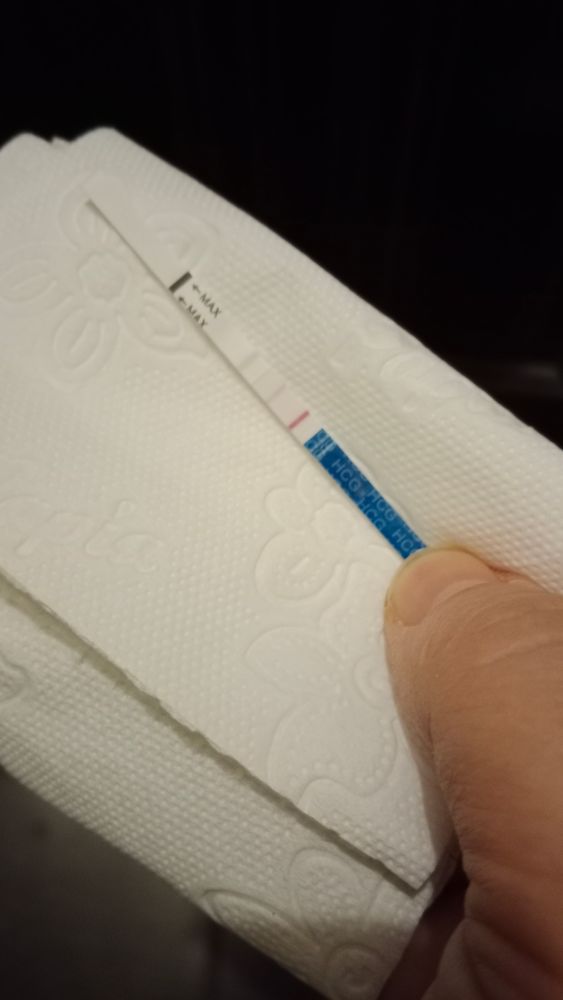

Не выдержала сбегала за эви.

Полоска есть но тоже слабая какая то для 9 дня задержки